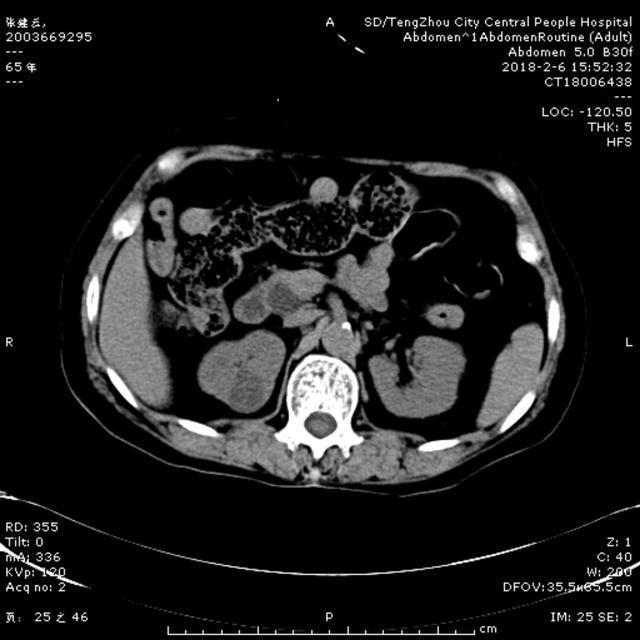

2月6日15:00,一65歲女性患者,因腹痛5天,伴寒戰(zhàn),發(fā)熱,惡心,嘔吐,在當(dāng)?shù)卦\所治療,效果差,以“腹痛待查”收住消化內(nèi)二科。入院查體:體溫37.1℃ 血壓140/90mmHg,急性病容,鞏膜輕度黃染,心肺未及異常,腹部平坦,右上腹壓痛伴反跳痛,肝區(qū)叩擊痛陽性,雙下肢無水腫。入院后給予抗炎、補(bǔ)液處理。急查肝功示谷丙轉(zhuǎn)氨酶561U/L, 谷草轉(zhuǎn)氨酶798U/L, 總膽紅素64.9umol/L ,直接膽紅素58.9umol/L,血常規(guī)示白細(xì)胞5.44X10^9/L, 中性粒細(xì)胞4.69X10^9/L,凝血常規(guī)示正常,行腹部CT可見膽囊壁增厚,膽總管擴(kuò)張,考慮膽系感染、 膽總管結(jié)石可能性大。